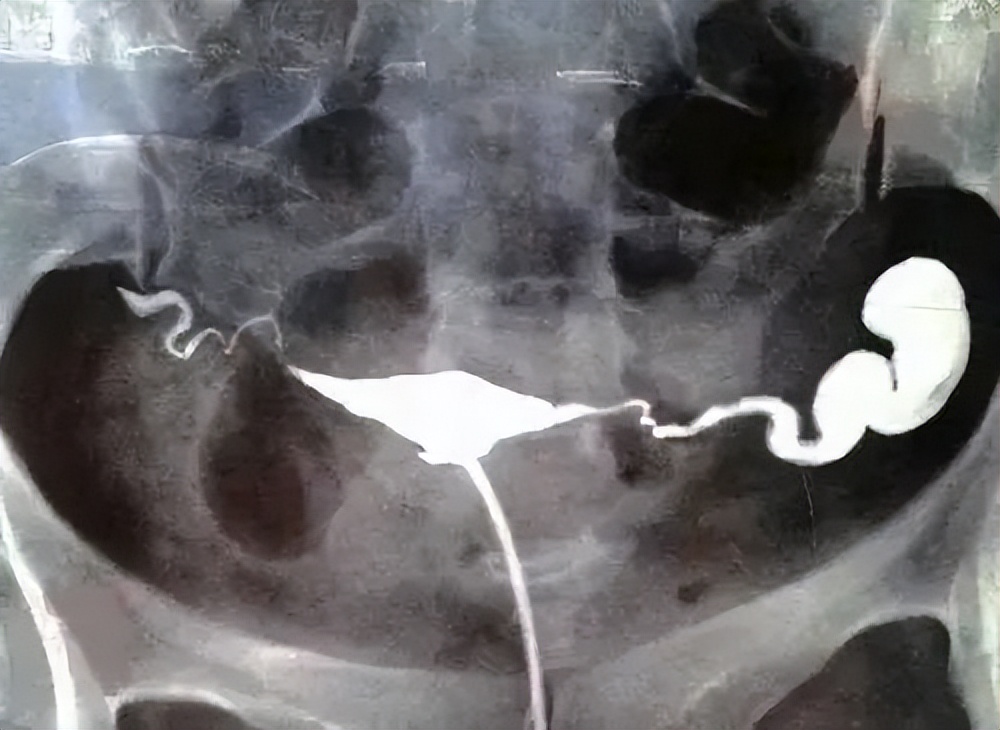

子宫输卵管造影是通过导管向宫腔及输卵管注入造影剂,让造影剂在子宫、输卵管和盆腔内流动、弥散,利用X线诊断仪行X线透视及摄片。

输卵管造影可以分为碘油造影;还可以分为碘水成像造影。可以有效诊断子宫先天性畸形及宫腔粘连、盆腔粘连等病理情况。